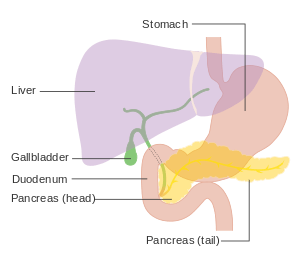

| Diagram showing the position of the pancreas, behind the stomach (which is transparent in this schematic). | |

Pancreatic cancer arises when cells in the pancreas, a glandular organ behind the stomach, begin to multiply out of control and form a mass. These cancerous cells have the ability to invade other parts of the body.[1] There are a number of types of pancreatic cancer. The most common, pancreatic adenocarcinoma, accounts for about 85% of cases, and the term "pancreatic cancer" is sometimes used to refer only to that type. These adenocarcinomas start within the part of the pancreas which makes digestive enzymes. Several other types of cancer, which collectively represent the majority of the non-adenocarcinomas, can also arise from these cells. 1-2% of cases of pancreatic cancer are neuroendocrine tumors, which arise from the hormone-producing cells of the pancreas. These are generally less aggressive than pancreatic adenocarcinoma.[2]